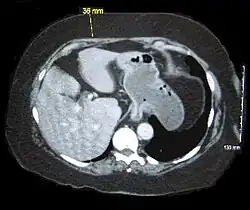

Abdominal computed tomography of an obese person showing excess abdominal adiposity